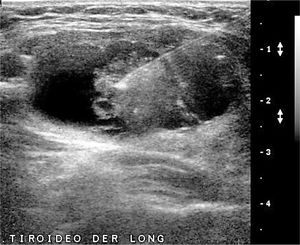

La disminución de tamaño del tiroides, sin antecedentes de cirugía, frecuentemente se debe a procesos inflamatorios crónicos de larga data. Por otra parte, frecuente en nuestra población, está el aumento de tamaño del tiroides: bocio, que puede ser difuso o nodular (uni o multinodular), causa de consulta médica general y segunda causa de consulta endocrinológica (Figura 5a y 5b).

Bocio.

A: Tiroides en un corte longitudinal, de forma globulosa aumentado de tamaño, contornos suavemente lobulados, parénquima hipoecogénico, heterogéneo, sin imágenes de nódulos en su espesor.

B: Tiroides en un corte longitudinal, globuloso aumentado de tamaño, contornos lobulados, hipoecogénico, heterogéneo, con nódulos sólidos de diferente tamaño.